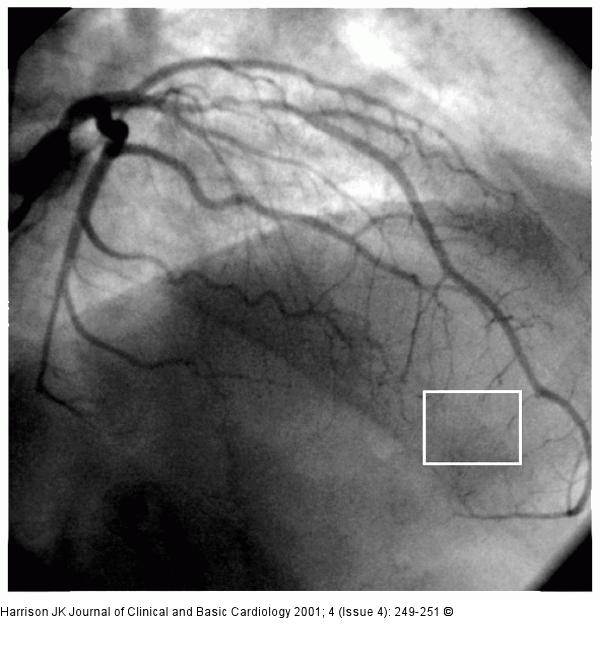

Figure/Graphic 1: R. interventricularis anterior - Stenose Left coronary angiogram in the right anterior oblique projection demonstrating stenosis in the proximal left anterior descending coronary artery. The box defines a region of interest, downstream to the coronary lesion, in which myocardial contrast blush can be measured |

Left coronary angiogram in the right anterior oblique projection demonstrating stenosis in the proximal left anterior descending coronary artery. The box defines a region of interest, downstream to the coronary lesion, in which myocardial contrast blush can be measured |